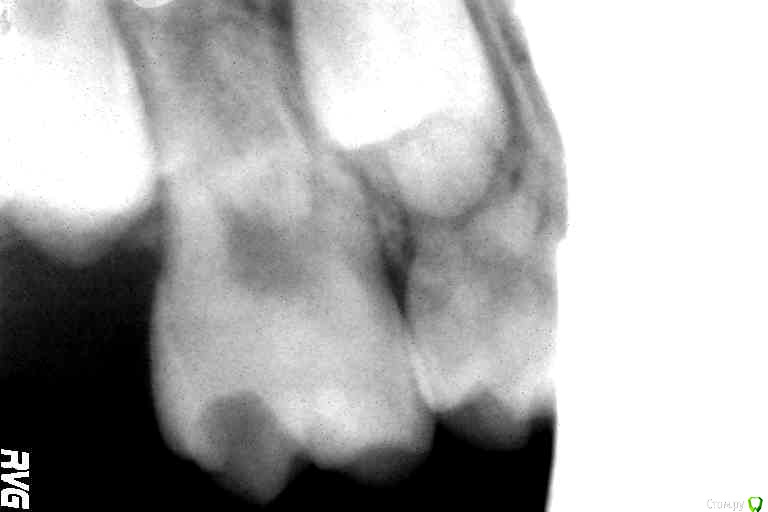

Уважаемые коллеги,обратилась девочка 8 лет на удаление молочного зубика, больше её ничего не беспокоило. Зубик удалил и нашёл ещё много чего интересного. Раньше не приходилось сталкиваться с таким мегаразрушительным кариесом. Да и вообще с чего начать, за что браться не представляю. Помогите пожалуйста. Все пломбы, что найдёте из Vitremerа, кроме той что на 1.6-там Nanopaq.

Зуб 2.6 думаю витально ампутировать, зуб 3.6 возможно тоже, но может обойдетесь МТА на рог пульпы. Остальные в плановом порядке лечить. Думаю, все будет ок)